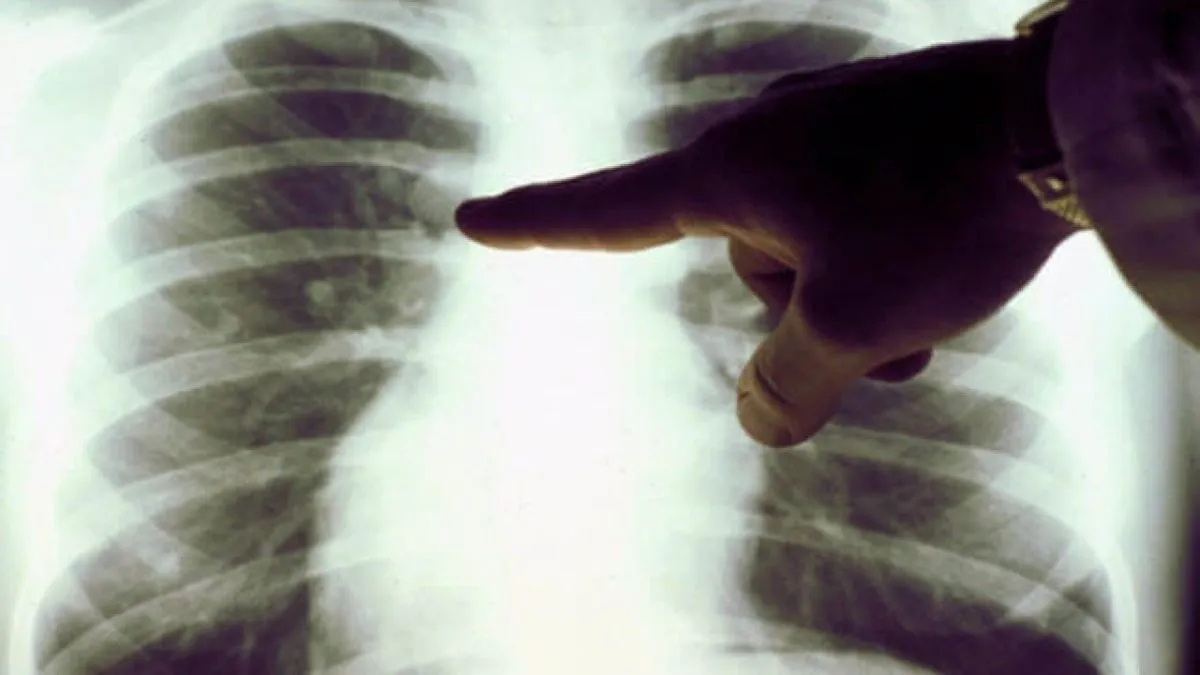

Легеневі захворювання, зокрема хронічне обструктивне захворювання легень (ХОЗЛ), є однією з провідних причин смертності у світі – 5%.

Важливо! В Україні на ХОЗЛ страждають близько 4% населення, а близько 2% смертей зумовлені саме цією патологією.

Основними причинами хвороб легенів, зокрема раку, є тютюнопаління (85% випадків) та забруднення повітря.

❗️Рак легень – найпоширеніший онкологічний вид у світі та провідна причина смертей від раку – 18,7% усіх онкосмертей.

В Україні щороку реєструють близько 13 тисяч нових випадків, причому чоловіки хворіють у п'ять разів частіше за жінок. Більш ніж у 70% пацієнтів хворобу виявляють на пізніх стадіях.